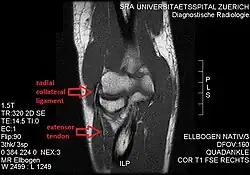

Radial collateral ligament of elbow joint

The radial collateral ligament (RCL), lateral collateral ligament (LCL), or external lateral ligament[Explain 1] is a ligament in the elbow on the side of the radius.

- the radial collateral ligament [proper] (RCL), from the lateral epicondyle to the annular ligament deep to the common extensor tendon[1]